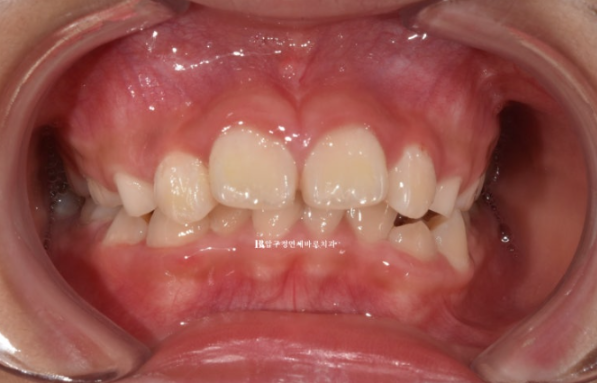

소아교정을 위해 찾아온 만 9세 어린이 입니다.

22.08

위 앞니가 아랫니를 가려서 안 보일 정도로 깊게 물리는 과개교합이고 윗니 돌출이 눈에 띕니다.